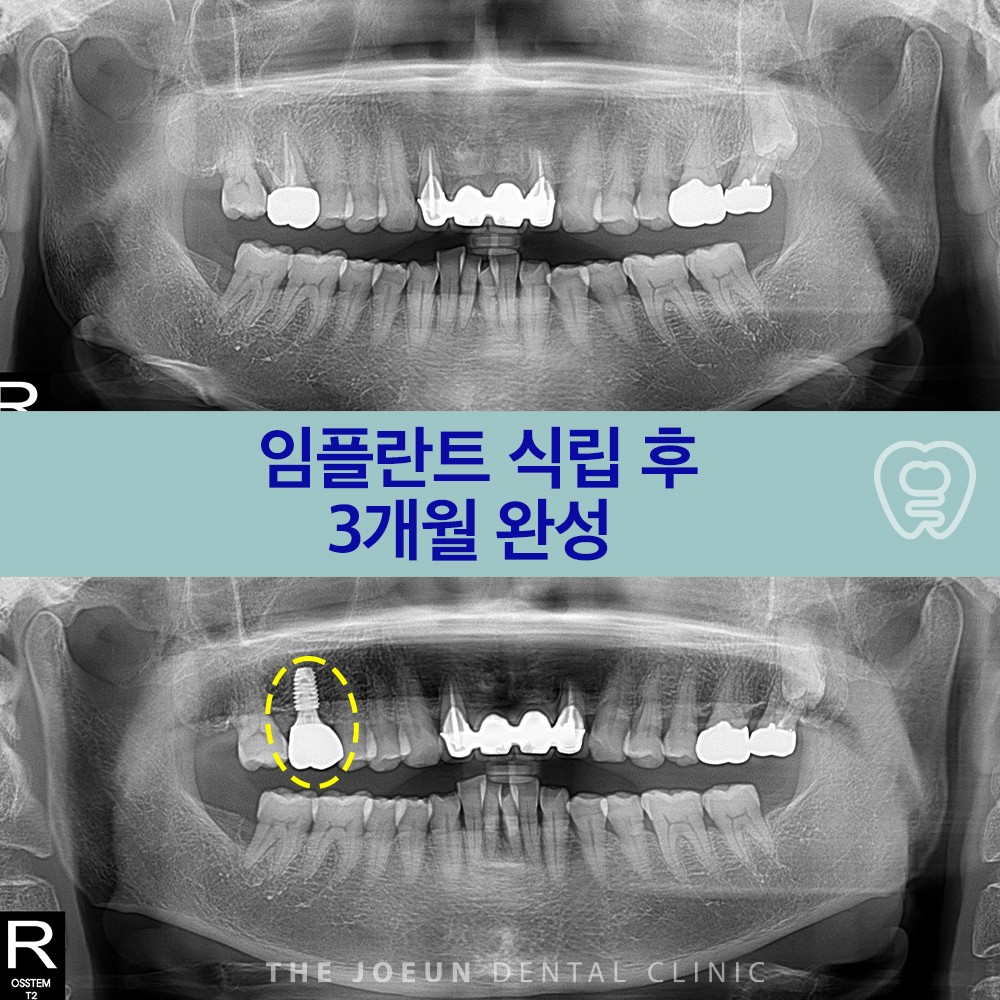

달서구치과 아래 앞니 발치 후 즉시 임플란트 3개월 완성

2025-10-31

달서구치과 아래 앞니 발치 후 즉시 임플란트 3개월 완성 치아는 저작 기능뿐 아니라 얼굴의 인상과…